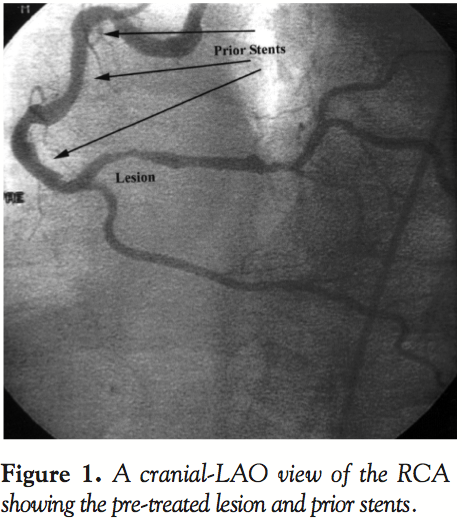

mm Tetra Stent was placed distally in overlapping fashion. Five months later, due to recurrent symptoms, the RCA was again found to have recurrent disease. The area of previously diagnosed mild distal disease now progressed to critical disease with a 90% minimally calcified stenosis distal to the prior stented segments, which were widely patent. PTCA was performed on the distal segment, leaving a less than 25% residual stenosis and no dissection. Despite multiple attempts with an assortment of guiding catheters (JR4, Hockey-stick, Amplatz, and Multipurpose), wires (hydrophyllic, extra-support, and soft) and techniques (femoral and brachial access), a stent could not be passed down the tortuous vessel, especially through the previously stented segments. One year later, the patient again developed recurrent disease in the same area of the RCA and again could only be treated with PTCA. Finally, one year later, recurrent disease in the same un-stented region of the RCA prompted another intervention (Figure 1). The lesion was again treated with PTCA via the femoral artery, however a novel wire designed to assist in the delivery of a stent in complex anatomical situations was used. An ACS Hi-Torque Wiggle Wire™ (ACS/Guidant, Santa Clara, Calif.) was advanced across the treated area and a 3.0 x 13 mm Penta Stent (ACS/Guidant, Santa Clara, Calif.) was easily advanced and deployed, resulting in successful treatment and 110% of pre-treatment lumen diameter (Figure 2). At nine months, the patient is completely asymptomatic.